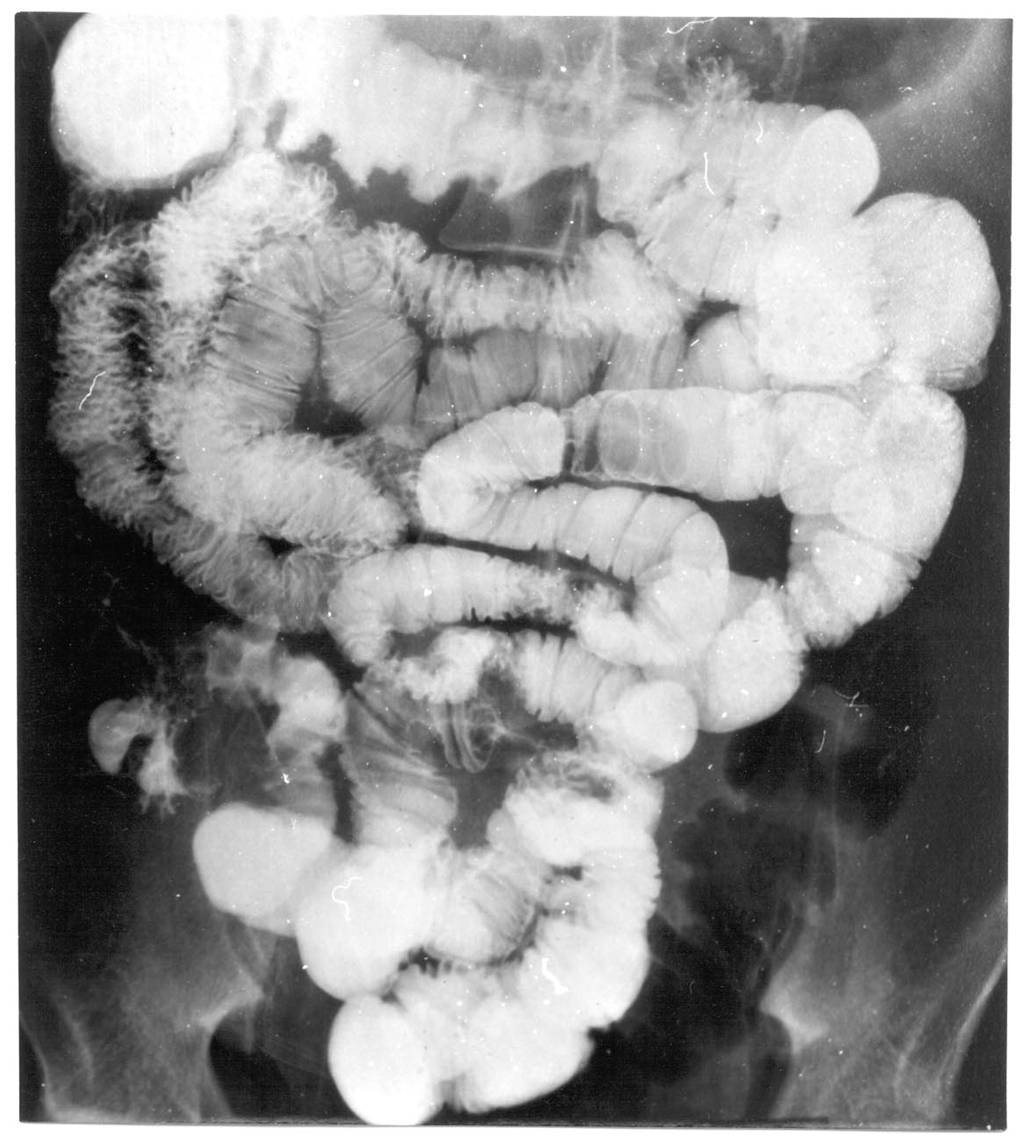

Image

Fig.20.: Follow-through examination

On the abdominal radiograph distension of the small bowel loops and air-fluid levels can be identified. It is important to describe forwarding of the contrast media by time or if mechanical obstruction is seen. Morphology of the intestinal loops could not be assessed with this method. This study is specifically conducted to examine the transit function only.